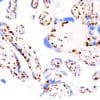

p53

p53, also known as tumor protein 53 or TP53, is a tumor suppressor and transcription factor that functions in a number of anti-cancer activities including DNA repair, cell-cycle arrest, and apoptosis in response to DNA damage or other stressors. Mutations in p53 are linked to a number of malignant tumors, including those of the breast, ovarian, bladder, colon, lung, and melanoma. Anti-p53 staining has been used to detect intratubular germ cell neoplasia, and also to distinguish between uterine serous carcinoma and endometrioid carcinoma.

| Positive Control | Colon Carcinoma |